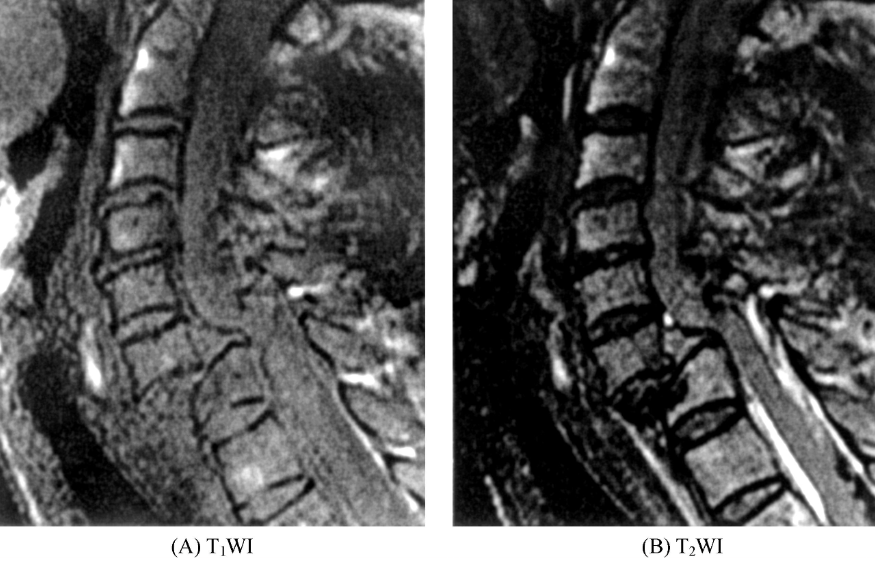

2、脊柱骨折:

MRI诊断

①椎体爆裂骨折。椎体呈楔形,矢状位和冠状位显示椎体上下缘皮质骨低信号带失去完整性,凹凸不平或部分嵌入椎体。椎体内信号改变,T1WI上呈低信号,T2WI上呈高信号,为渗出和水肿所致。骨折线于T1WI及T2WI上均表现为线状低信号影(图3),横断位可见骨折片向各个方向移位。

图3 椎体爆裂骨折胸7椎体楔形变,T1WI上信号减低,T2WI上信号增高,内见线状短T1长T2信号影,胸5~胸8椎体水平脊髓内见条片状长T1长T2信号影。